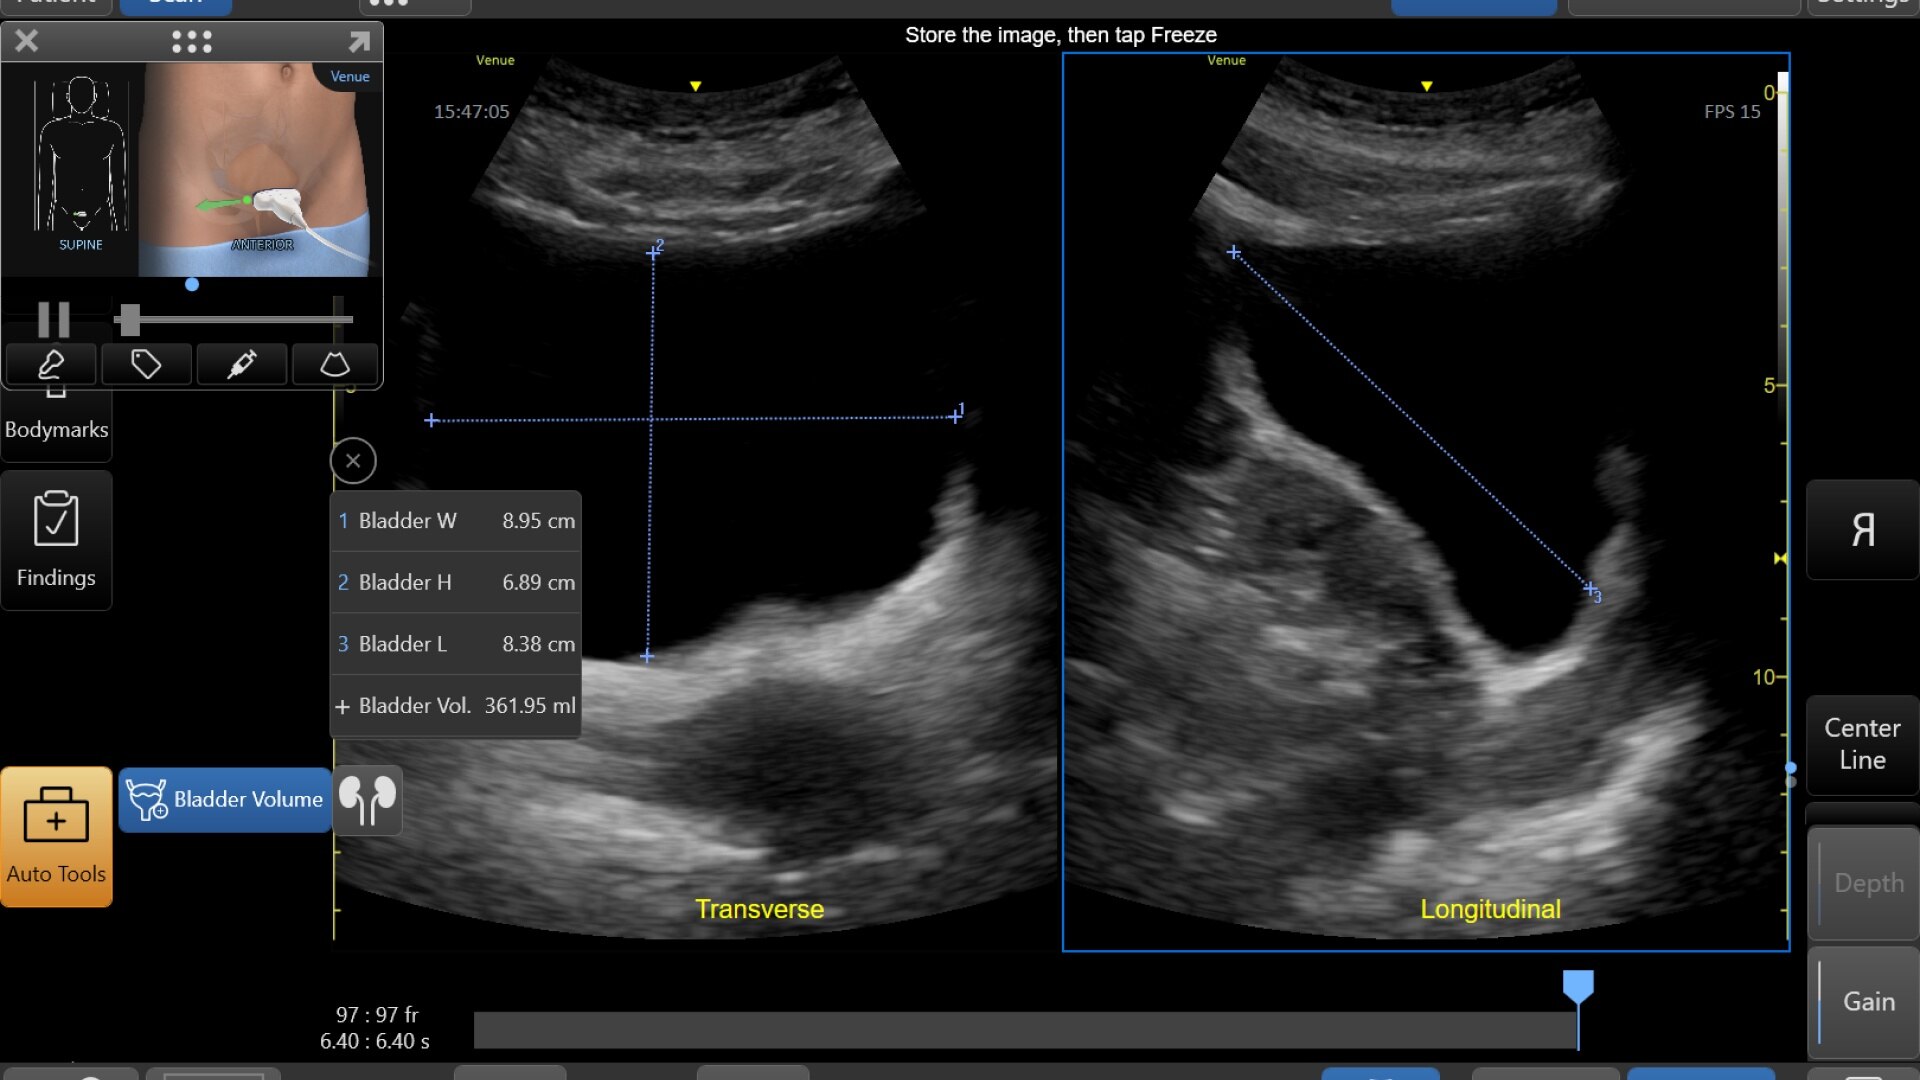

AI-DRIVEN AUTO TOOLS

Advanced and automated clinical tools enabling you to quickly diagnose, treat and determine a care pathway.

Venue Go has been designed and tested to be walk up easy for novice to expert users, and it features a number of AI-enabled automated tools to accelerate clinical workflow while also reducing the fatigue of repeated and difficult tasks. Utilizing proprietary algorithms, we synthesize data from numerous patients to ensure accurate calculations for clinical confidence.